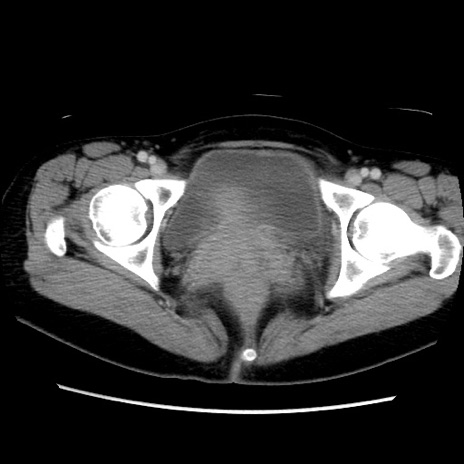

症例39(横断像)

【症例】40歳代女性

【主訴】上下腹部痛

【現病歴】2日目から下腹部痛あり。夜間は痛みで眠れなかった。昨日より上腹部痛と下痢が出現。臥位で痛みは軽快したため、休んでいた。本日になって臥位でも立位でも痛みが強くなってきたため救急要請。

【既往歴】子宮内膜症

【身体所見】部:平坦・軟、左上下腹部に圧痛あり、反跳痛あり。

【データ】WBC 21800、CRP 26.78